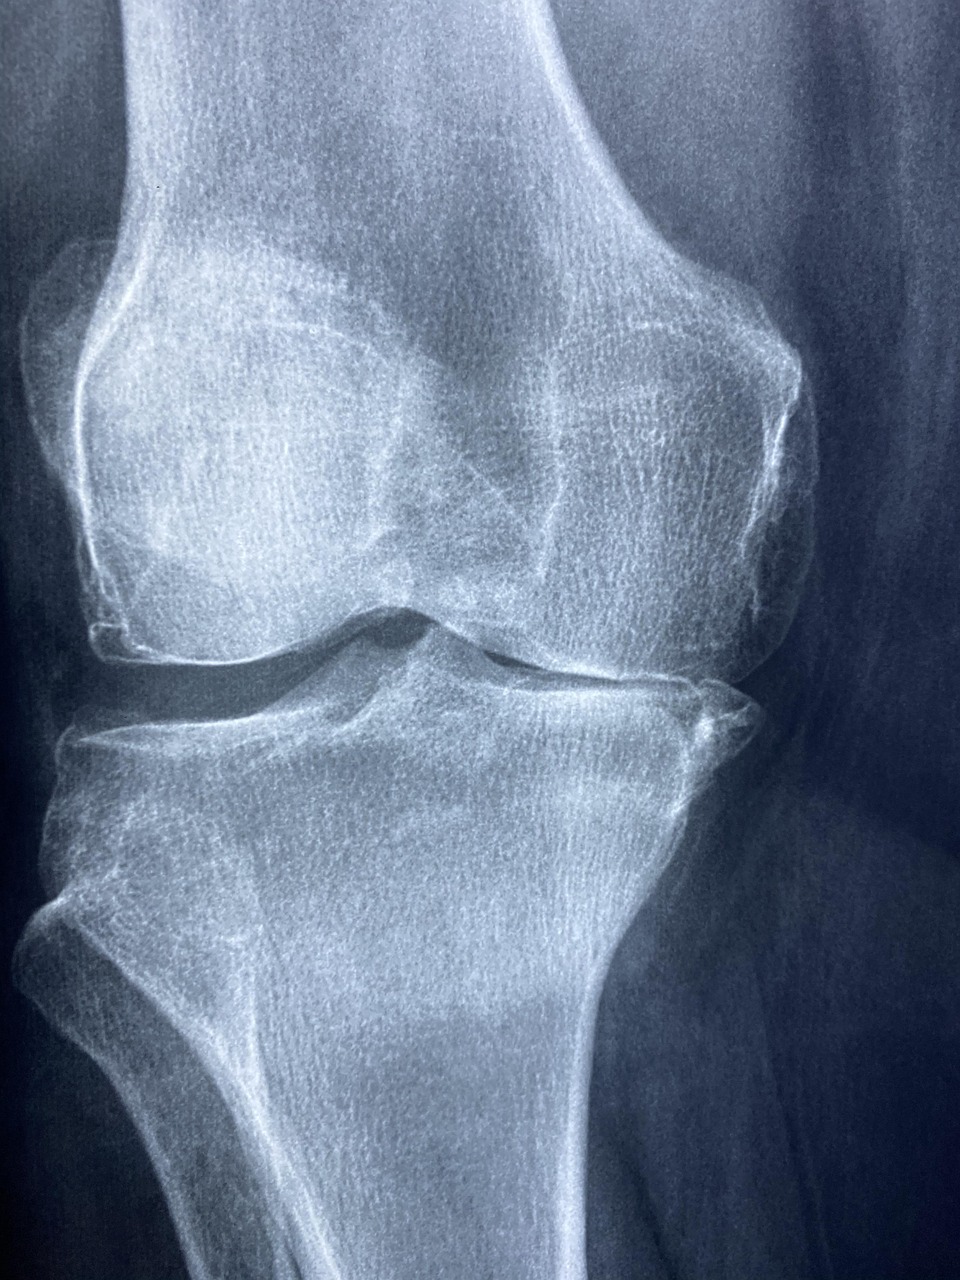

❓ 인공관절 수술이란?

- 정의: 손상된 관절(무릎, 고관절 등)을 금속·플라스틱 재질의 인공관절로 대체하는 수술

- 대상: 퇴행성 관절염 말기, 고관절 괴사, 외상성 골절 등